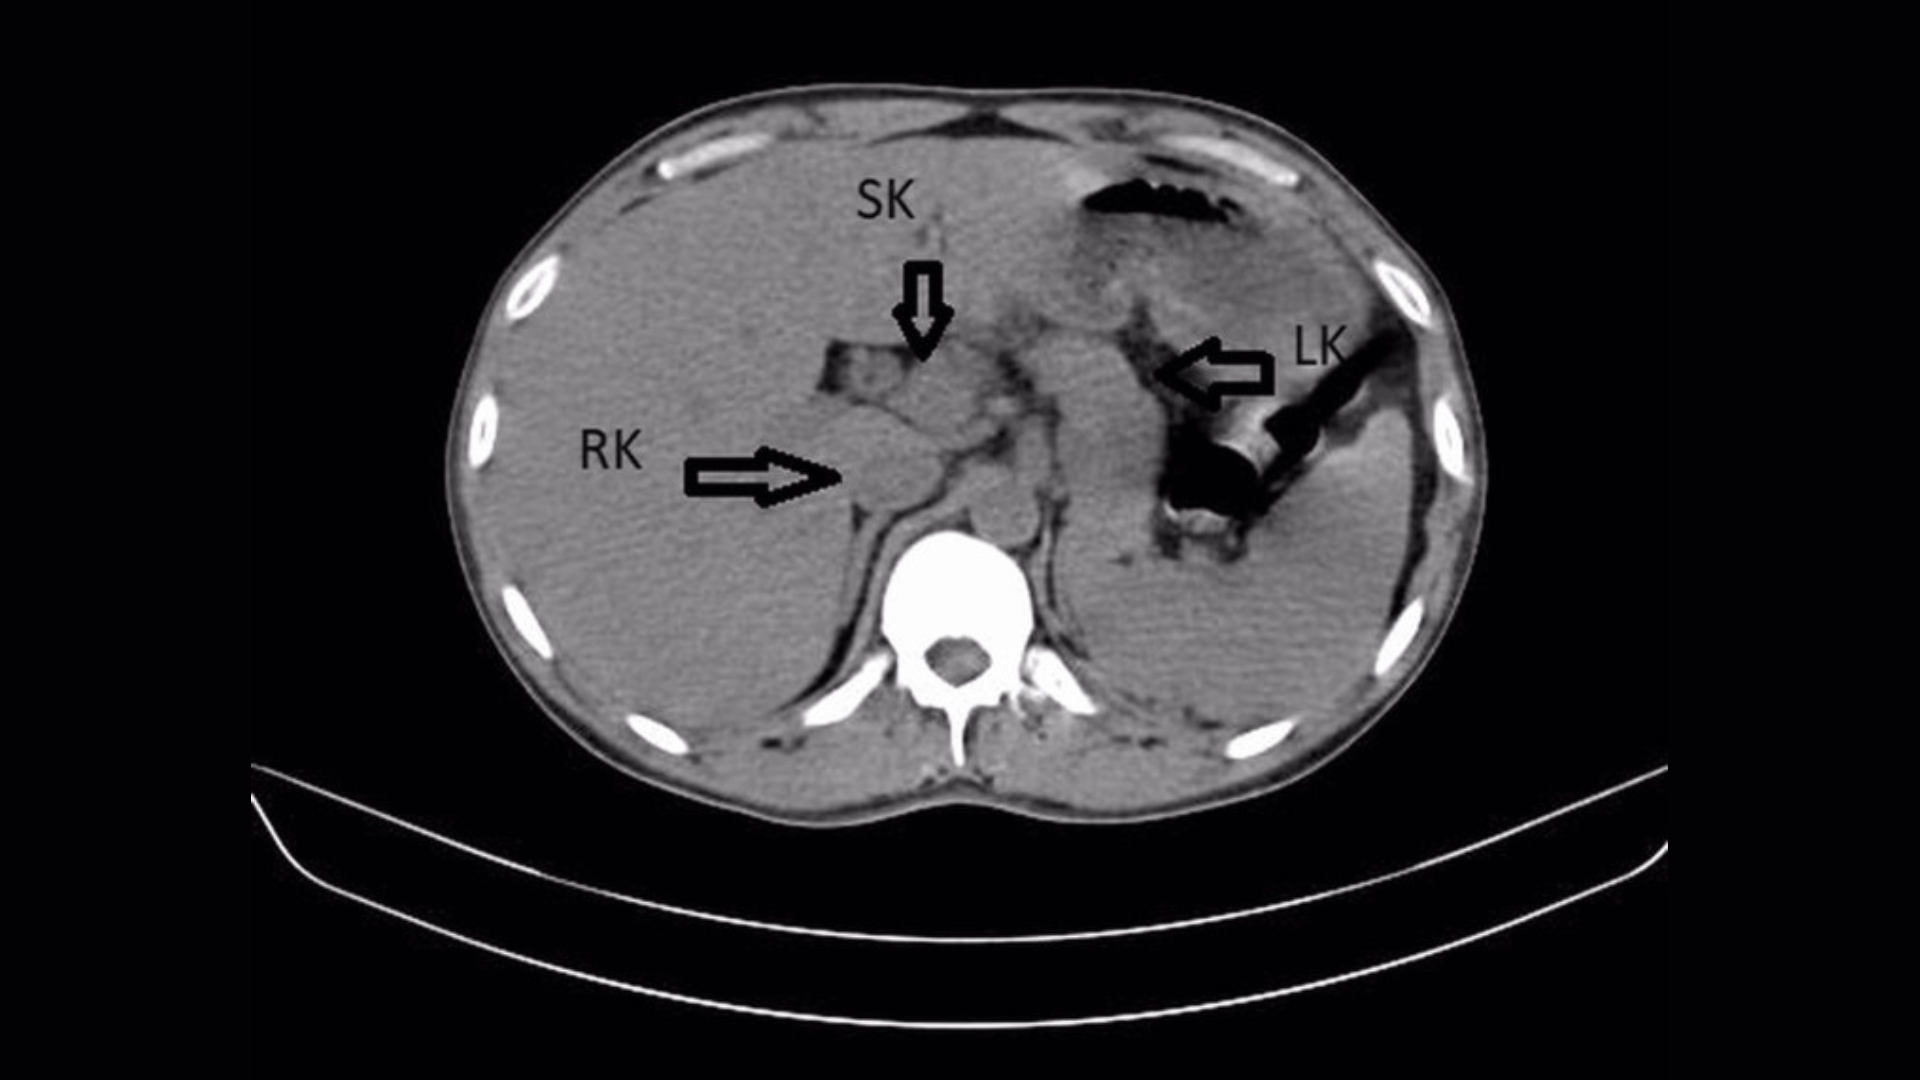

Mais en plus, une échographie et un scanner de l’abdomen du patient ont révélé quelque chose d’inattendu : un troisième rein, également appelé rein surnuméraire. Il a été fusionné au rein droit de l’homme, créant ainsi une forme de fer à cheval.

Un rein surnuméraire est une anomalie congénitale qui apparaîtrait au cours du développement fœtal. Cela apparaît en raison d’une division cellulaire anormale dans la moelle qui forme plus tard les reins. Un rein surnuméraire peut conduire parfois à des infections rénalesmais cette maladie n’affecte pas toujours la fonction rénale normale et passe souvent inaperçue, selon le rapport.

Dans ce cas, les reins gauche et droit du patient étaient enflés et présentaient des accumulations de tartre ou de cristaux minéraux. Ces cristaux durs se forment lorsque l’urine est plus concentrée ; les petits « calculs » disparaissent souvent normalement pendant la miction, mais peuvent entraîner une infection s’ils persistent dans les reins sans traitement.

Ce qui rend le cas unique : Les reins surnuméraires sont extrêmement rares, avec moins de 100 nouveaux cas signalés dans le monde chaque année.

Une fusion en « fer à cheval » avec un autre rein est encore plus rare, avec seulement cinq cas rapportés dans la littérature scientifique. Les troisièmes reins peuvent également être complètement séparés ou vaguement reliés à un autre rein par une fine couche de tissu.